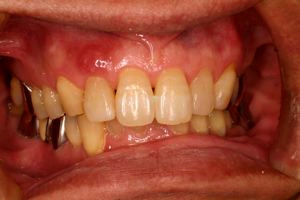

インセラム(オールセラミック)症例①

治療前治療前インセラム(オールセラミック)冠による修復。 主訴は前歯が汚い 金属を使わないオールセラミックでの治療を勧めた。 術前 治療後治療後術後

インセラム(オールセラミック)症例②

治療前治療前術前 治療後治療後術後 歯の尖端の透明感までよく再現できている。